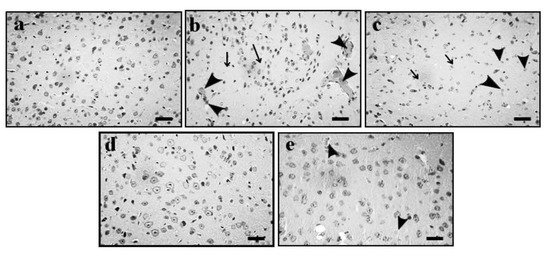

2.4. Effect of GE on AD-Induced Histopathological Changes